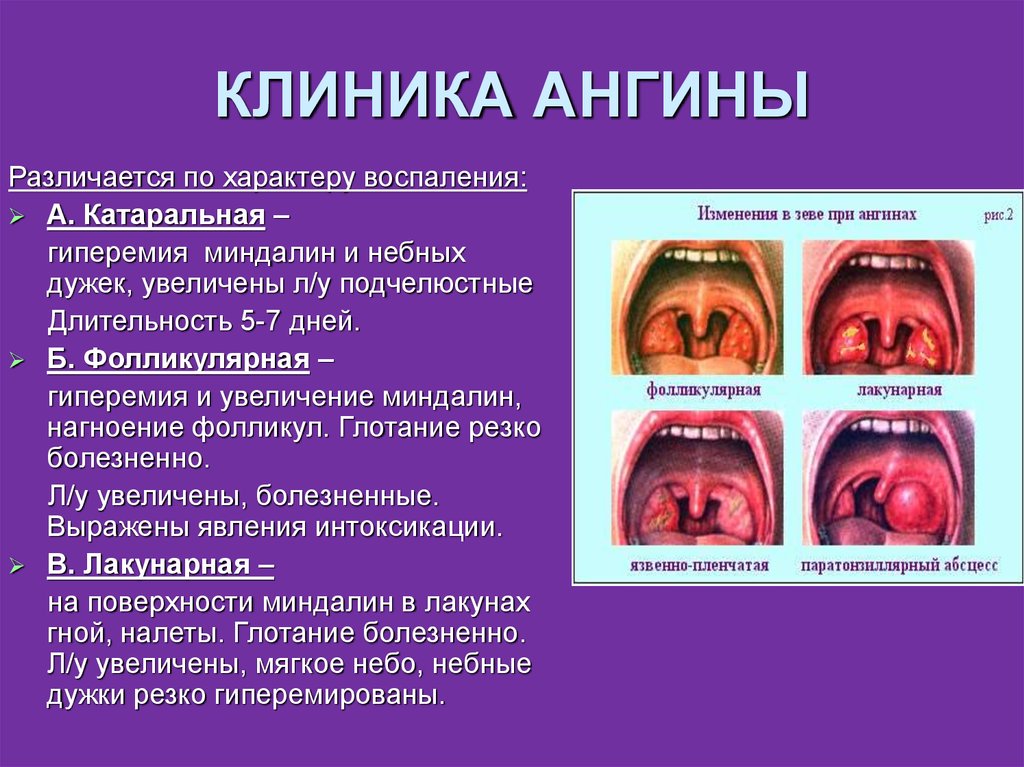

Клиническое течение при ангине у каждого ребенка может отличаться, учитывая тип заболевания:

- Катаральная, которая является наиболее распространенной и протекает легче, чем другие типы болезни. Проявляется поверхностным поражением миндалин с появлением небольших красных участков на слизистой оболочке. Симптоматика выражена не остро, при этом возможно незначительное повышение температуры до 37-38°С. Ребенку часто ставится такой диагноз при развитии заболеваний верхних дыхательных путей.

- Фолликулярная или гнойная. Отличается более острым течением, часто сопровождается высокой температурой – 38°С и выше. При подобной форме на миндалинах можно обнаружить небольшие белые или желтые гнойники не больше 2 мм. При гнойной ангине увеличиваются и болят при пальпации лимфоузлы на шее и затылочной части.

- Лакунарная. Характерным признаком является ярко выраженная клиническая картина, при этом гнойные образования локализуются на протоках небных миндалин (лакунах).

Если организм ослаблен, бактерии могут проникнуть в миндалины и начать размножаться, вызывая патологические изменения в лимфоидной ткани. Это приводит к развитию катарального воспаления, которое может прогрессировать в гнойный процесс. В результате возникает фолликулярная ангина, которая характеризуется наличием гнойных изменений в фолликулах. При осмотре зева видна “звездная” картина, где на гиперемированном фоне можно увидеть точечные скопления гноя белого или беловато-желтого цвета. Процесс продолжается, гнойные фолликулы вскрываются, гной вытекает и проникает в лакуны, где образуется новый очаг воспаления, что приводит к лакунарной ангине.

Разделение на фолликулярную и лакунарную формы условное, поскольку часто обе стадии диагностируются одновременно. По клиническому течению они практически не отличаются, разница заключается только в фарингоскопической картине. При осмотре зева видны лакуны, заполненные гноем, которые имеют неправильную форму и напоминают поверхность “гриба мухомора”

- катаральная. При осмотре зева видно, что небные дужки, миндалины увеличены и покрыты серозным белесоватым налетом;

- фолликулярная. Характерным признаком является наличие гнойных точек на миндалинах, размер которых может быть до трех миллиметров;

- лакунарная. Осмотр зева, открывает отекшие и сильно покрасневшие миндалины, покрытые налетом гноя, желтого цвета;